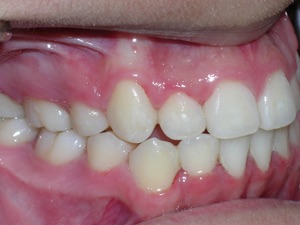

Here is what he looked like on the day that the braces were removed.

In the final photo, you can see the bonded retainer we used. A top nighttime removable retainer was made.